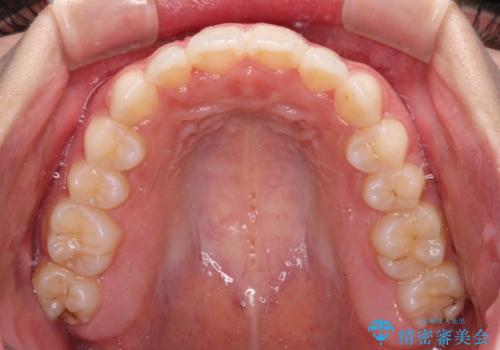

【モニター】前歯のクロスバイトをインビザラインで治療

- 前歯のデコボコとクロスバイトを気にして来院された患者様です。

上顎側切歯(上の真ん中から2番目の歯)が舌側転位している場合、インビザラインでは仕上げきれないことが多く、更には無理して動かそうとすると歯髄壊死を起こすリスクが高いと言われています。

今回は、ワイヤー装置を併用することなく、インビザライン単体で矯正治療を行うこととしました。

インビザライン特有の、奥歯の咬み合わせの問題もなく、しっかりと歯列を改善することができました。

舌側転位している上顎側切歯(内側に引っ込んでいる真ん中から2番目の歯)は、インビザラインが最も移動を苦手とする歯であり、これ以上の改善を望まれる場合にはワイヤー矯正、あるいはワイヤー矯正の併用をお勧めいたします。